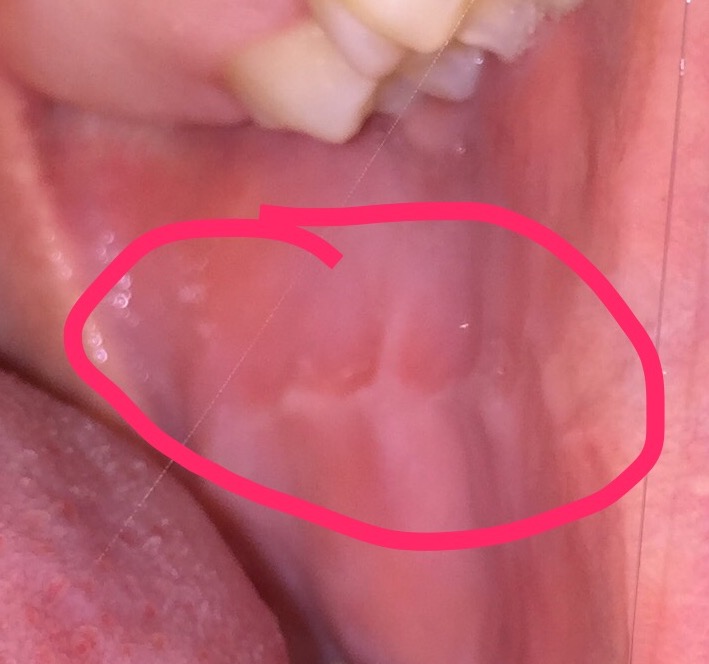

Salve. Sono un ragazzo di 20 anni e scrivo in provincia di Genova. Studio giurisprudenza e sono molto amante della vita nonostante sia io un po' ipocondriaco. Ho notato da un po' che la mucosa nelle mie guance è strana. Già da anni con la lingua (nella guancia destra addirittura già da bambino, in quanto ho avuto prima di mettere l'apparecchio problemi per cui mi schiacciavo la mucosa fra i denti e ho avuto lesione per anni da bambino ma si è rimarginata subito dopo messo apparecchio che ha portato indietro la dentizione) sentivo la mucosa un po' dura. Da tempo la sento anche nella sinistra questa ruvidità. Mia madre, farmacista sostiene sia la mia mucosa fatta così in quanto sono simili queste strisce di colore differente. Non ho dolore o altro vivo bene mangio e bevo senza fastidi. Da tempo però mi preoccupo perché nonostante avessi questa ruvidità da tempo non avevo mai notato questa formazione diversa con i miei occhi. Ho paura si tratti di lesioni precancerose dato che leggevo impiegano molto tempo per portare la mucosa a canceroginarsi (se esiste questo termine). Non nascondo che sono fumatore ma le mucose dure le sentivo già prima di fumare. Ho iniziato a settembre con il fumo quindi non è nemmeno un anno che fumo. Questo non significa ovviamente che faccia bene fumare da poco. Vorrei semplicemente capire se ho una mucosa fatta così (visto che è da bambino che la sento ruvida e sono anni per cui, almeno 12 che la sento così) o se devo preoccuparmi di morire giovane per un cancro o altra patologia della mucosa orale. Allego foto scattate in macro con iPhone, spero si vedano bene. Ringrazio anticipatamente,

IMG_6513.JPG

IMG_6514.JPG